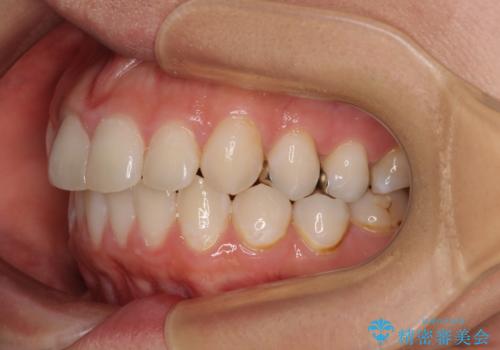

- 口元の突出感と奥歯のむし歯を気にして来院された患者様です。

奥歯の虫歯は事前に矯正治療用の仮歯に置き換えて矯正治療を行い、装置除去後にセラミッククラウンにて補綴治療を行うこととしました。

通常は上下左右の第一小臼歯4本を抜歯することになりますが、左側下顎の第二小臼歯は既に根管治療をされており、予後が良くないとのことでこの歯を抜歯し、ワイヤー装置にて矯正治療を行うこととしました。